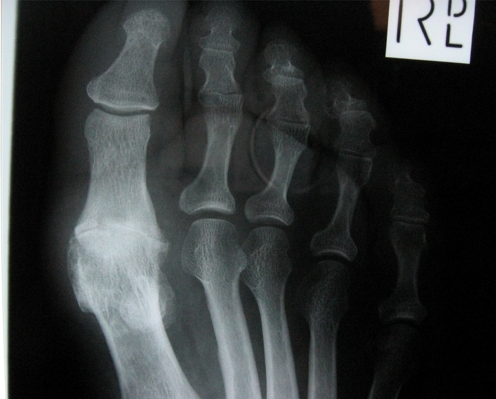

Clinical image for Hallux Rigidus

How would you classify hallux rigidus? What clinical and radiographic features differentiate each grade?